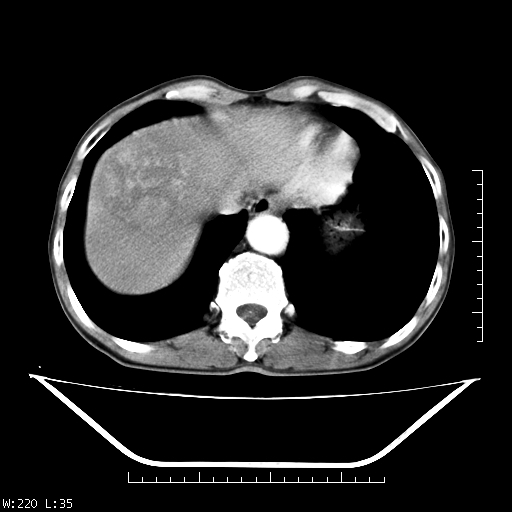

男,70,右上腹痛两月,有乙肝病史,b超提示肝占位,ct如下,请会诊。

肝右叶类圆型密度减低影,密度不均,边界清晰其内可见更低密度影,腹膜后可见小淋巴结肿大,增强扫描动脉期病灶明显强化,静脉期及延时扫描见强化不明显,快进快出表现。

平扫呈低密度占位,动脉期斑片状明显强化,病灶边缘清晰,见假包膜;门脉期呈低密度,符合肝癌快进快出强化特征

补充:该患者afp 9.24,似乎与原发性肝癌不符合,另胰头区结构正常吗?请大家继续发表高见。